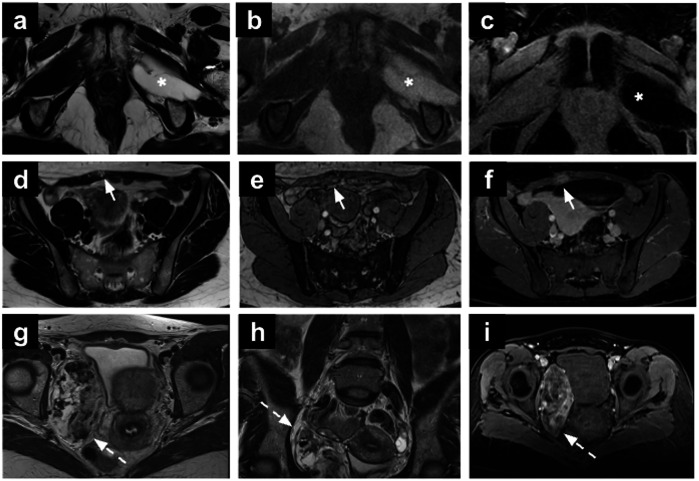

女性骨盆MRI的偶然发现给诊断带来了挑战,并可能具有重要的临床意义。定义为与主要影像学指征无关的异常,随着MRI在妇科实践中的广泛应用,这些发现变得越来越普遍。标准的妇科MRI方案,包括T1和t2加权序列,弥散加权成像和对比增强序列,促进了许多妇科外异常的特征,从良性到严重病变。这篇综述提出了一种基于区隔的方法来识别妇科外的发现,讨论他们的影像学特征和鉴别诊断。这种方法可以帮助放射科医生系统地评估偶然发现,潜在地提高对临床相关异常的认识,并支持及时的临床决策。关键相关性声明:骨盆MRI附带的妇科外发现可能会带来重大的诊断挑战。系统评估骨盆MRI附带的妇科外发现可以提高放射科医生对临床相关异常的认识。重点:骨盆MRI的妇科外偶然发现是常见的,范围从良性到恶性。基于腔室的分类——将女性骨盆分为前腔室、侧腔室、后腔室、肌肉骨骼腔室和其他腔室——为解释骨盆提供了一个系统的框架。全面评估所有MRI序列,包括大视场图像,可能有助于确定临床相关的偶然发现。

Incidental findings on female pelvic MRI present diagnostic challenges and may have significant clinical implications. Defined as abnormalities unrelated to the primary imaging indication, these findings have become increasingly prevalent with the expanded use of MRI in gynaecological practice. Standard gynaecological MRI protocols, incorporating T1- and T2-weighted sequences, diffusion-weighted imaging, and contrast-enhanced sequences, facilitate the characterisation of numerous extra-gynaecological abnormalities, ranging from benign to critical lesions. This review proposes a compartment-based approach for identifying extra-gynaecological findings, discussing their imaging characteristics and differential diagnoses. This approach may help radiologists systematically assess incidental findings, potentially improving the recognition of clinically relevant abnormalities and supporting timely clinical decision-making. CRITICAL RELEVANCE STATEMENT: Incidental extra-gynaecological findings on pelvic MRI can present significant diagnostic challenges. Systematic evaluation of incidental extra-gynaecological findings on pelvic MRI can improve radiologists' awareness of clinically relevant abnormalities. KEY POINTS: Extra-gynaecological incidental findings on pelvic MRI are common and range from benign to malignant conditions. A compartment-based classification-dividing the female pelvis into anterior, lateral, posterior, musculoskeletal, and miscellaneous compartments-provides a systematic framework for interpretation. Thorough assessment of all MRI sequences, including large field-of-view images, may help identify clinically relevant incidental findings.